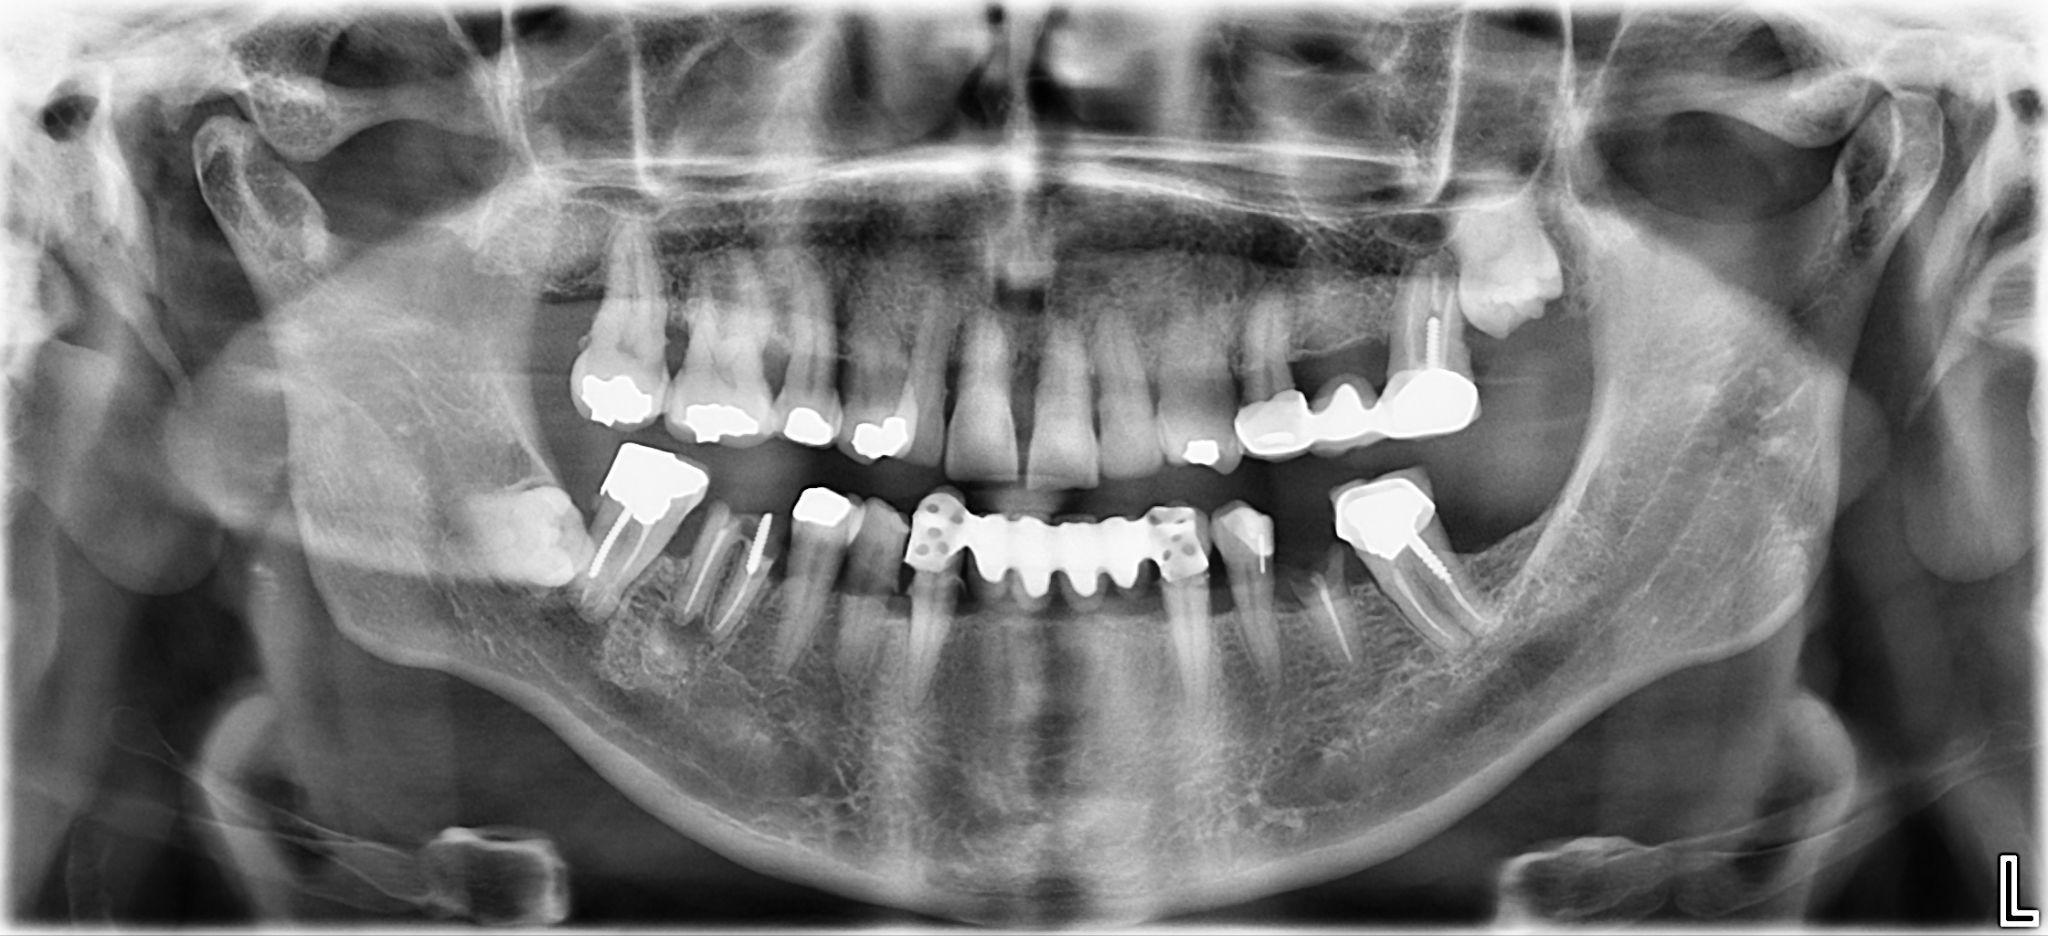

10. What option cannot be selected for the first quadrant of this panoramic X ray?

11. What option cannot be selected for the second quadrant of this panoramic X ray?

12. What option cannot be selected for the third quadrant of this panoramic X ray?

13. What option cannot be selected for the forth quadrant of this panoramic X ray?

14. What option cannot be selected for the upper jaw of this panoramic X ray?

15. What option cannot be selected for the lower jaw of this panoramic X ray?